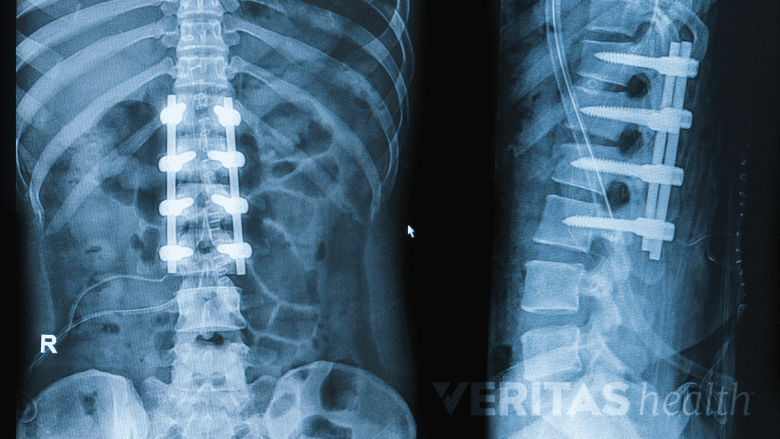

Multilevel Spinal Fusion: Fusing 2 or More Spinal Motion Segments

A multilevel spinal fusion involves fusion 2 or more spinal segments.

Some fusion surgeries may involve fusing 2 or more motion segments of the spine to become one single unit. This type of surgery is called a multilevel spinal fusion.

Multilevel spinal fusion is almost always performed on contiguous spinal levels.